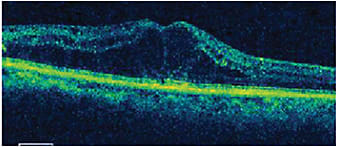

Given the patient’s poor response to anti-VEGF monotherapy, she was switched to a combination of Lucentis followed by the dexamethasone intravitreal implant (Ozurdex, Allergan) 2 weeks later. At the start of the combination therapy, the patient’s visual acuity was 20/100, and her CFT was 565 µm (Figure 1).

Figure 1. Prior to starting combination therapy, visual acuity was 20/100, and CFT was 565 µm.